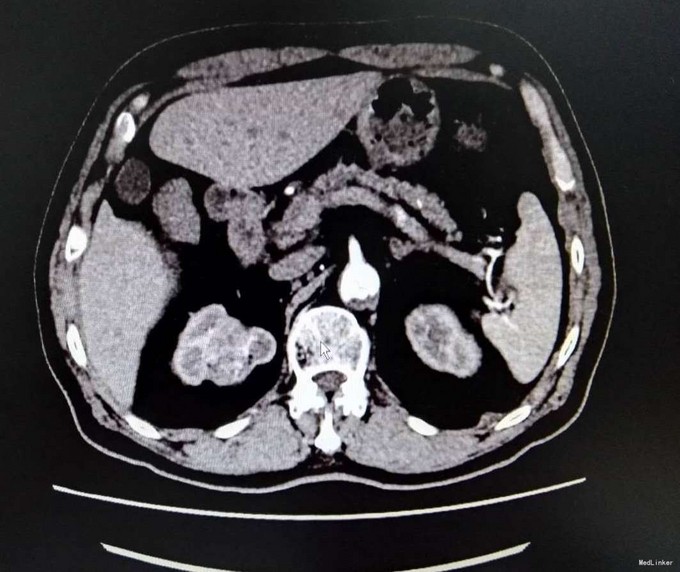

3、查体:无明显阳性体征 4、辅助检查:生化:肌酐:144umol/L。双肾CT平扫+增强:右肾上部肿块,考虑肾癌可能性大,ECT示:左肾 GFR 21.6ml/min,右肾GFR为22.3ml/min

5、肾癌 6、患者入院后完善相关检查,具体检查如上述,未见明显禁忌症,与患者及其家属充分沟通后,行腹腔镜下右侧肾癌根治术,术中未明显出血,术后患者恢复良好,术后病理提示肾透明细胞癌,患者顺利出院